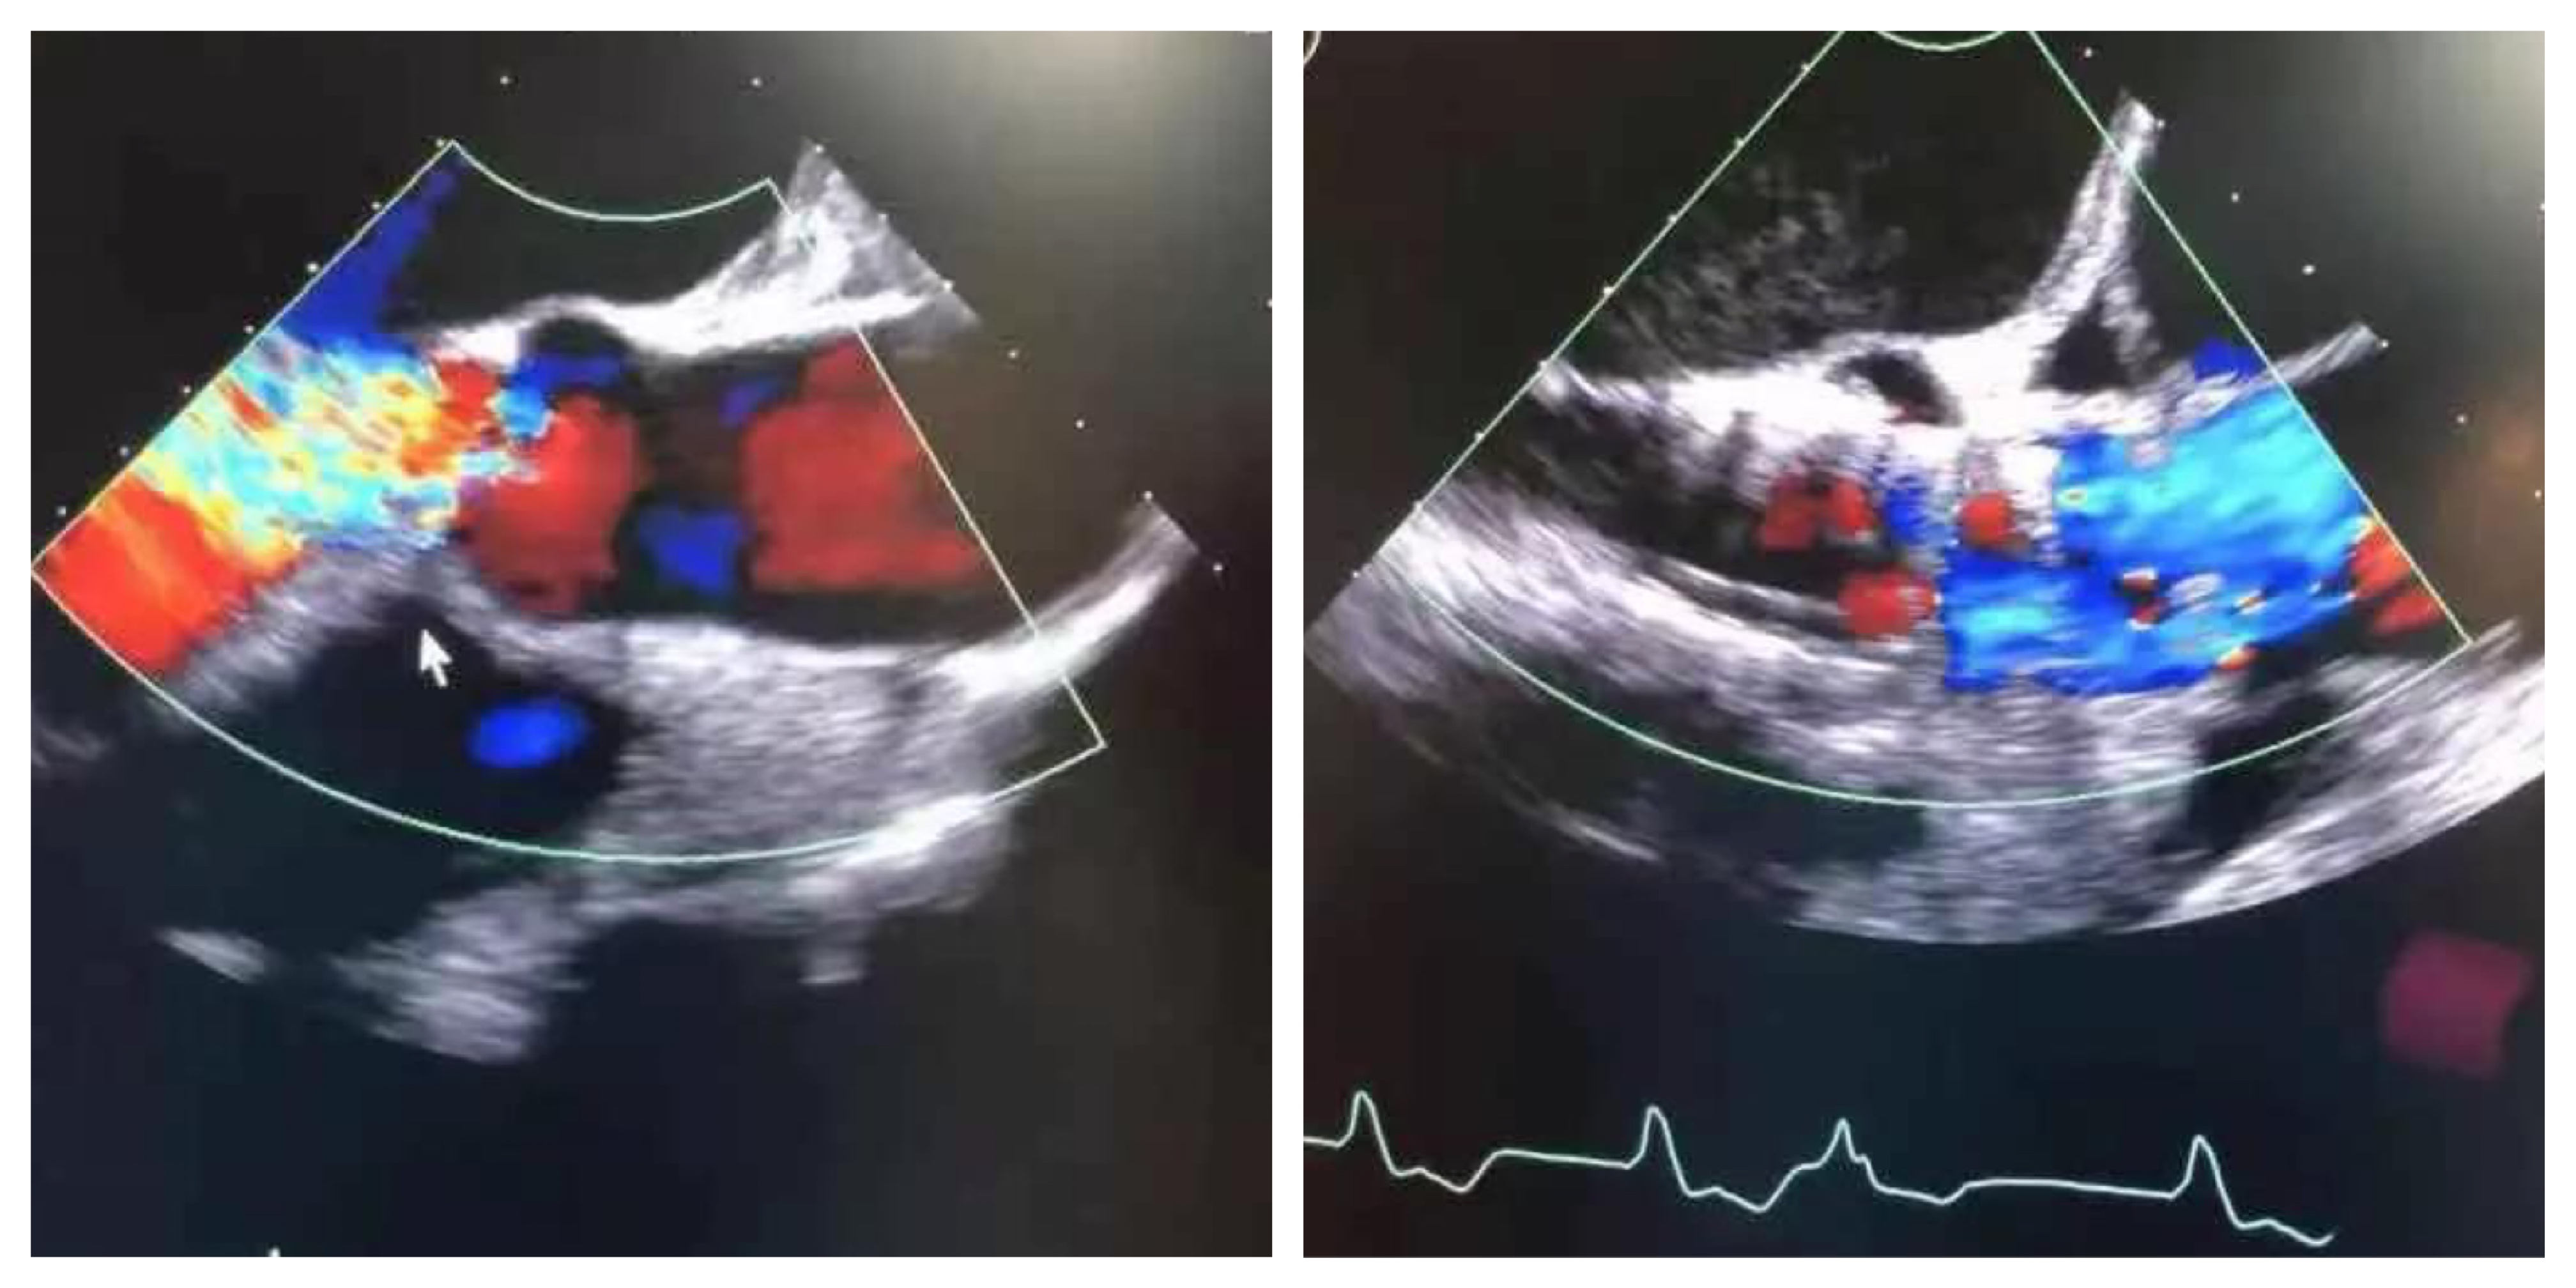

术前心超 术后心超